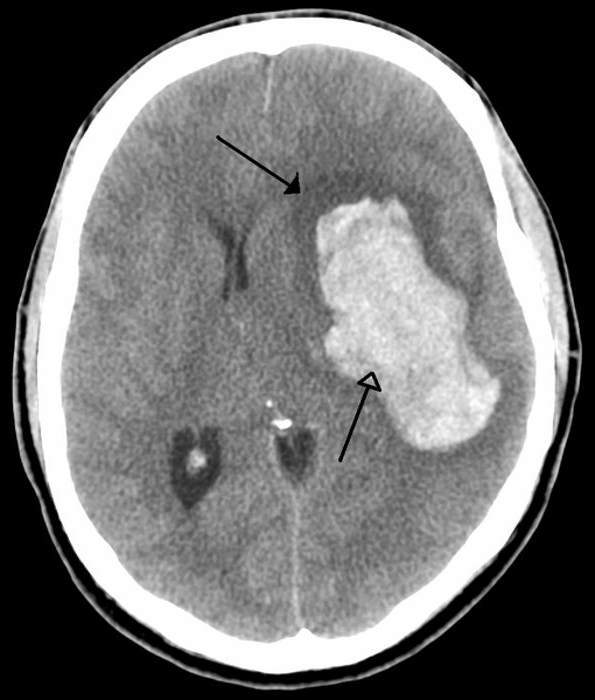

Сопор и кома при инсульте - Инсульт . РеабилитацияВнутримозговая гематома в результате геморрагического инсульта.

Принято считать, что внутримозговое кровоизлияние – удел старости, однако доля работоспособного населения по данному заболеванию значительно возрастает и вместе с тем затрудняет диагностику. Возникновению геморрагического инсульта у молодых способствуют:

В качестве неблагоприятных исходов геморрагического инсульта зачастую встречаются: нарастание отека мозга с его последующей дислокацией, рецидивы кровоизлияния, инвалидизация. В целом, на это влияет ряд отягощающих факторов:

1. Объемные гематомы;

2. Сопутствующее внутрижелудочковое кровоизлияние;

3. Локализация гематомы в стволе головного мозга, где находятся сердечно-сосудистый и дыхательный центры;

4. Сопутствующие заболевания сердечно-сосудистой системы;

5. Прием средств, разжижающих кровь накануне возникновения заболевания.